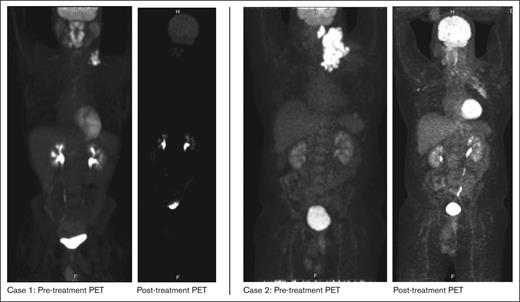

A male aged 23 years with asthma noticed left neck swelling which progressively worsened with associated fevers, chills, night sweats and weight loss. Computed tomography (CT) imaging of neck, chest, abdomen, and pelvis revealed disease localized to bilateral cervical lymph nodes (LN). Excisional biopsy of left cervical LN was notable for ALK+ LBCL with immunohistochemistry (IHC) stains showing positive ALK (cytoplasmic and golgi pattern), EMA, MUM1, weak CD45, weak CD79a, and CD138 (subset), with remaining stains shown in Table 1. Positron emission tomography-CT (PET/CT) revealed disease in palatine tonsil, adenoids, base of tongue, and left cervical and supraclavicular (SCV) LN. Bone marrow biopsy was negative for lymphoma involvement. He completed 3 cycles of CHOP (cyclophosphamide, doxorubicin, vincristine, and prednisone). Subsequent PET/CT revealed Deauville score of 4 in left cervical and SCV LN, thus the patient was started on crizotinib 250mg twice daily about 3 weeks after CHOP. He subsequently received localized radiation therapy to left cervical LN and a follow-up PET/CT after 3 months showed near CR. Surveillance CT scans every 6 months have shown ongoing CR while on crizotinib therapy. He has maintained a durable response to crizotinib for at least 6 years. His course has only otherwise been complicated by an incidental finding of a left subsegmental pulmonary embolism (PE), which was found on a surveillance scan in December 2019 and was managed with 3 months of rivaroxaban.

A male aged 46 years with hypertension and obstructive sleep apnea presented with 2-months of an enlarging left neck mass. He had no constitutional symptoms at the time. CT neck and chest were notable for enlarged left cervical and supraclavicular (SCV) LN with maximum diameter of 10.7 cm. Core biopsy of left cervical LN revealed ALK+ LBCL with IHC positive for ALK (granular cytoplasmic pattern), CD45, CD138, weak PAX5, and weak CD30; and IHC negative for CD20, CD3, CD5, CD8, S100, and MCK. PET/CT revealed an FDG-avid conglomerate left neck mass extending into the upper mediastinum and SCV region (SUV max 29) along with a left parapharyngeal lesion. He was, therefore, diagnosed with ALK+ LBCL, stage II, bulky disease. The patient received 1 cycle of CHOP. Within 15 days, he noticed worsening left neck swelling that was confirmed as clinical progression. Despite a dexamethasone burst (40mg daily for 4 days), he had no symptomatic relief and was urgently treated with radiation to the left neck mass (50 Gy/ 20 fractions). Within a few days after the completion of radiation therapy, he noticed a new left axillary LN. CT imaging confirmed enlarged bilateral axillary lymphadenopathy with reduction in left SCV LN. For systemic relapse, we were able to get approval for crizotinib 250mg twice daily, which he began approximately 1 month after radiation completion. The patient noted a drastic improvement in axillary lymphadenopathy within days. Upon initiation of crizotinib, there was a transient rise in liver function tests (AST 151 U/L, ALT 323 U/L) that resolved with hydration and conservative management. PET/CT completed approximately 8 weeks after radiation therapy noted a PR. However, about 2 months after crizotinib use, he reported enlarging bilateral axillary lymphadenopathy. PET/CT at this time confirmed interval PD in bilateral axilla along with a new left pleural effusion and minimally FDG-avid pulmonary nodules. He was referred back to radiation oncology and began localized radiation to the left axilla (50 Gy/ 20 fractions) and was switched to alectinib 600mg twice daily around the same time. Post-treatment PET/CT has revealed resolution of left axillary LN, ongoing reduction in left cervical LN, and mixed response within right axillary LN. He maintained PR on alectinib for 6 months but subsequently developed relapsed disease predominantly in the right axilla and right SCV nodes. Right axillary biopsy confirmed ALK+ LBCL with immunohistochemical stains negative for CD30 and CD19. TEMPUS testing from lymph node biopsy was only notable for CLTC-ALK rearrangement and copy number loss of ATM. He began focal radiation to right axilla, and for systemic therapy, was switched to lorlatinib 100 mg daily which he has been on for at least 6 months with evidence of complete metabolic response on PET. His course was otherwise complicated by coronavirus disease 2019 (COVID-19) with incidental findings of a left lower lobe subsegmental PE that was managed with apixaban.

In summary, we report the first case series of adult patients with ALK+ LBCL who were treated with ALK inhibitors and attained meaningful and durable clinical responses. Both our patients had diseases that were resistant to standard-of-care treatment with CHOP. Initiation of an ALK inhibitor led to a rapid clinical response in both patients as demonstrated in Figure 1. Our first patient from case 1 has done exceptionally well with crizotinib as demonstrated by ongoing CR for >6 years without any dose-limiting toxicities. In contrast, our second patient, after an initial response, had PD after 3 months of crizotinib therapy and, thus, was switched to a second-generation ALK inhibitor, alectinib. He tolerated this well with response lasting 6 months and now in a CR while being treated with lorlatinib currently again in a CR after progressing while on alectinib.